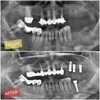

فقدان الأسنان

التهاب محيط الزرعة

التهاب مخاطية محيط الزرعة

علاج الزرع